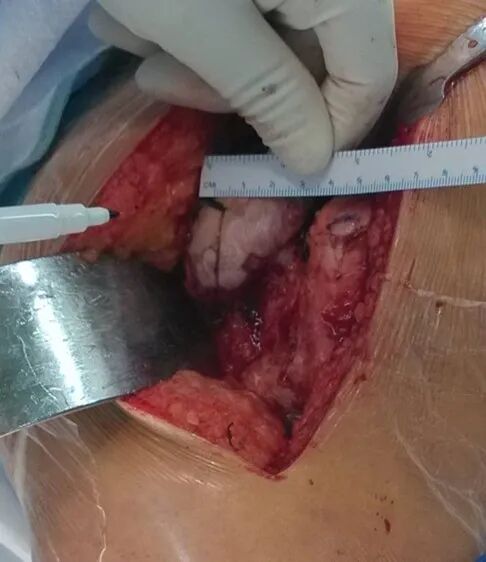

切开复位